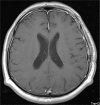

Giant Intracranial Solitary Plasmacytoma